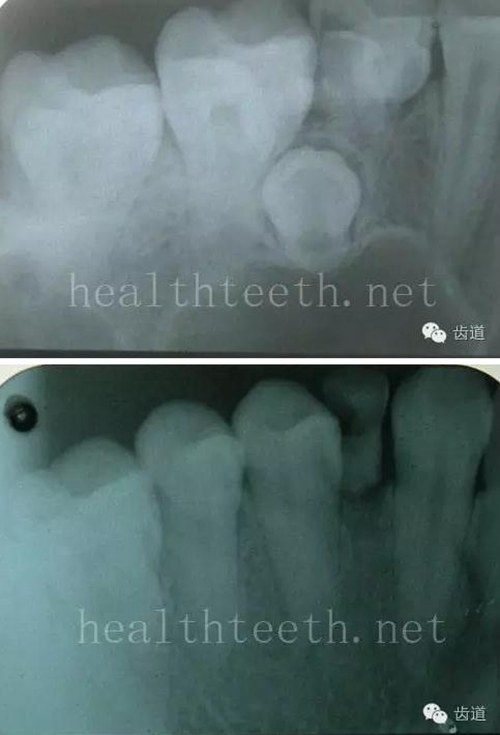

二、牙周組織病

牙片顯示牙槽骨的垂直吸收

外院做的牙周固定,牙片顯示牙槽骨的水平吸收